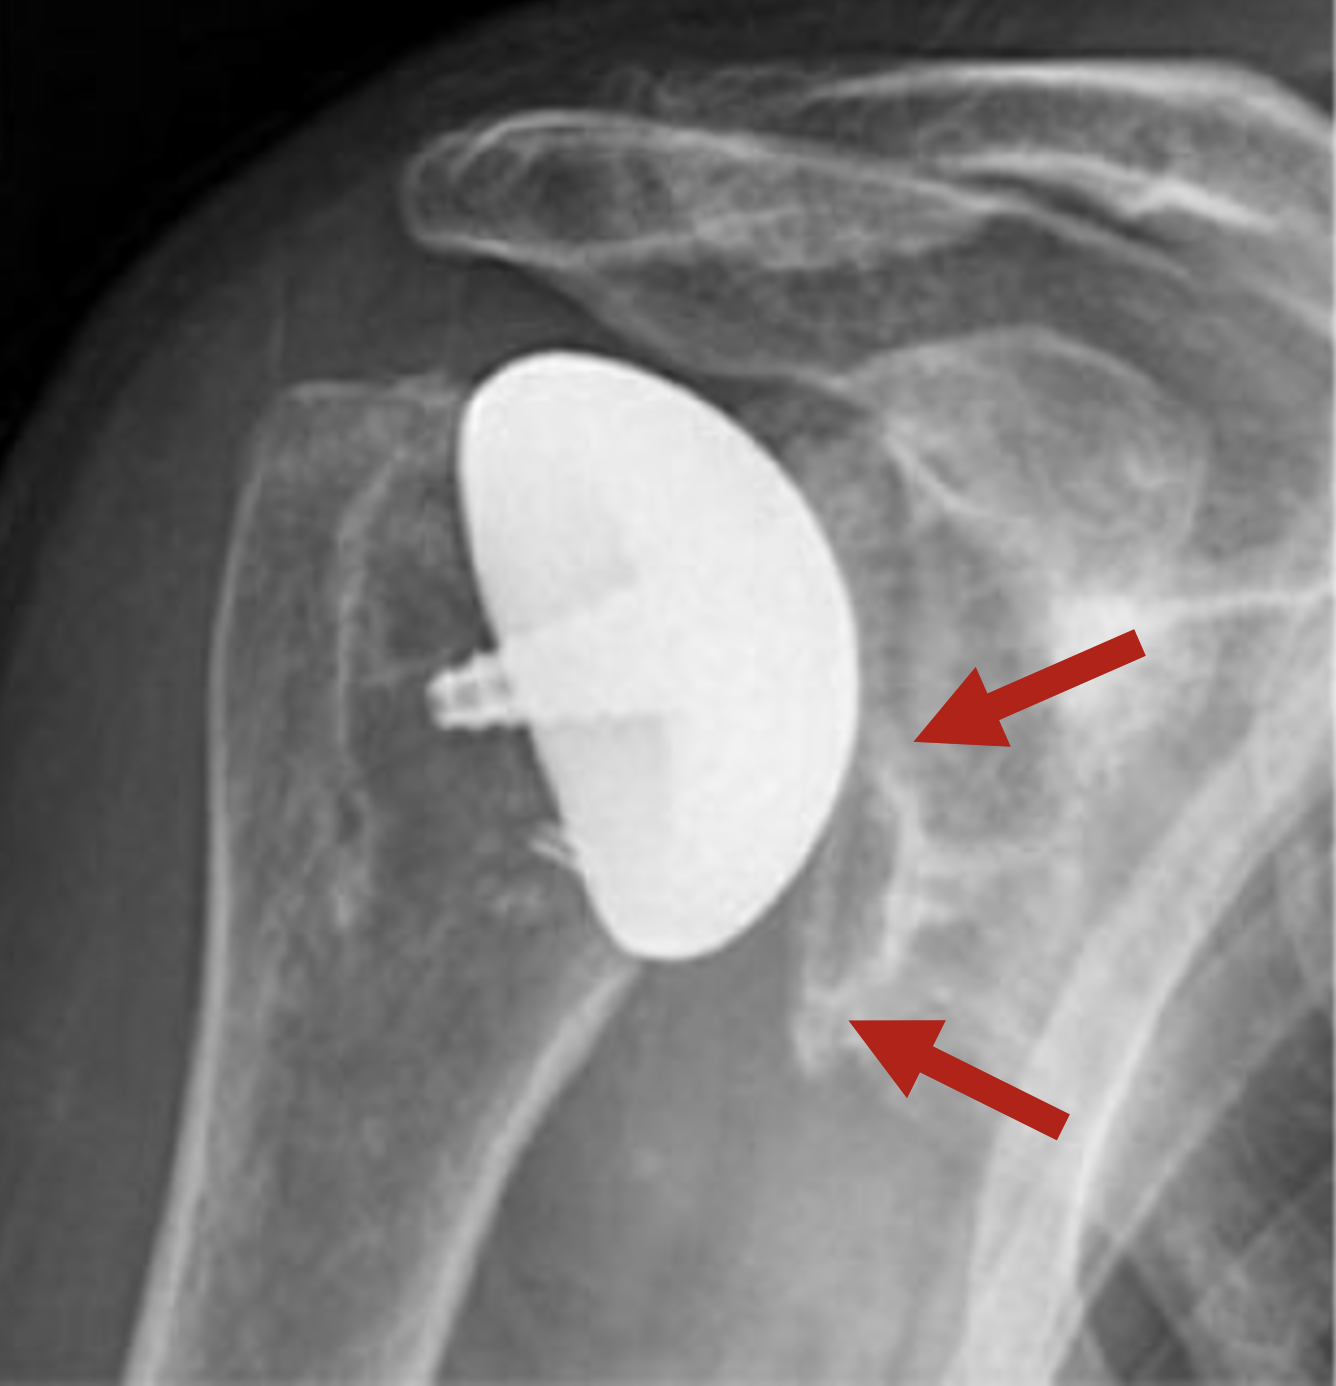

UW Shoulder and Elbow Academy The inlay glenoid arthroplasty in weight Inset Glenoid inset glenoid fixation technology offers a paradigm shift away from classic surface onlay implants to a new clinically proven,. more recently, inset glenoid designs have been developed. inset glenoid fixation technology offers a paradigm shift away from classic surface onlay. prior reports on inlay or inset glenoids were coupled with spherical hh replacement: Inset™ design to. Inset Glenoid.